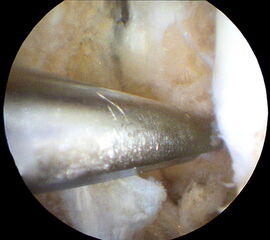

Nachfolgend wird die OP-Technik an einem rechten Sprunggelenk unter Verwendung von PEEK-Ankern veranschaulicht.

-

Abbildung 4 -

Abbildung 5 -

Abbildung 6 -

Abbildung 7a -

Abbildung 7b -

Abbildung 8a -

Abbildung 8b -

Abbildung 9a -

Abbildung 9b -

Abbildung 10 -

Abbildung 11 -

Abbildung 12 -

Abbildung 13 -

Abbildung 14 -

Abbildung 15 -

Abbildung 16 -

Abbildung 17 -

Abbildung 18 -

Abbildung 19 -

Abbildung 20 -

Abbildung 21 -

Abbildung 22 -

Abbildung 23 -

Abbildung 24 -

Abbildung 25a -

Abbildung 25b